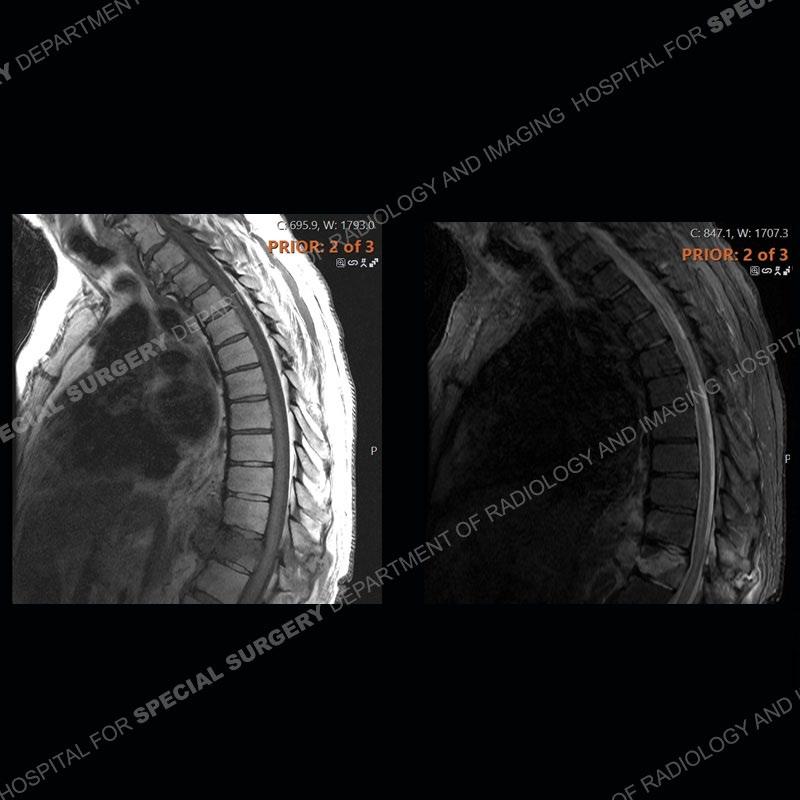

The initial MRI shows edema with a subtle fracture of the T11 vertebral body extending into the posterior elements. The subsequent MRI demonstrates a persistence and increased edema of the T11 body and posterior elements, anterior paraspinal edema/hematoma, and a progressive loss of the architecture of the T11 vertebrae. Seen well on the axial images of the MRI is the loss of CSF of the thecal sac/severe stenosis and severe right neural foraminal stenosis. The CT examination shows the loss of architecture of T11 from continued fracture and collapse. Well seen also is paravertebral osteophyte formation with bony bridging and bony bridging of the facet joints. There is an overall relative preservation of the disc spaces.

Diagnosis: DISH fragility fracture